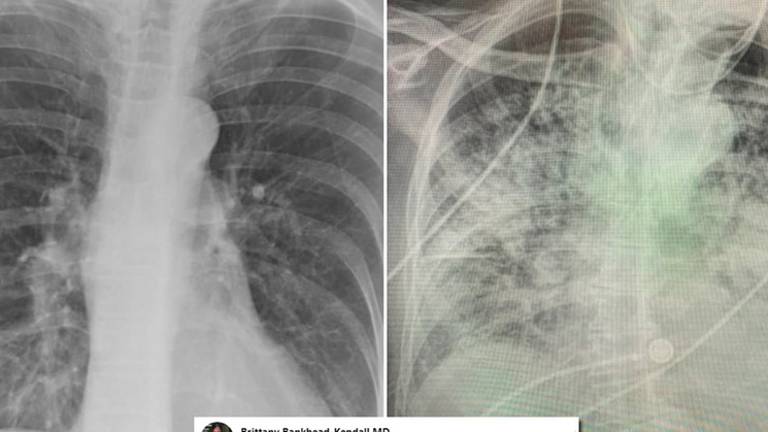

Para ello, la especialista comparó radiografías de los pulmones de pacientes normales, con covid y fumadores y el resultado es alarmante, pues, según compartió en su cuenta de Twitter, “los pulmones post-covid se ven peor que cualquier tipo de pulmón de fumador que hayamos visto. Y colapsan. Y se coagulan. Y la falta de aire persiste y no para”, afirmó Brittany Bankhead-Kendall, profesora asistente de la Universidad Técnica de Texas.

Los pulmones de un paciente sano deberían verse limpios y con mucho espacio negro, que es básicamente aire, mientras un pulmón de un fumador tiene líneas blancas, como una especie de neblina, que son indicativas de cicatrización y congestión.

Sin embargo, los pacientes post covid, muestran pulmones que parecen estar casi completamente blancos, en otras palabras, severamente dañados.